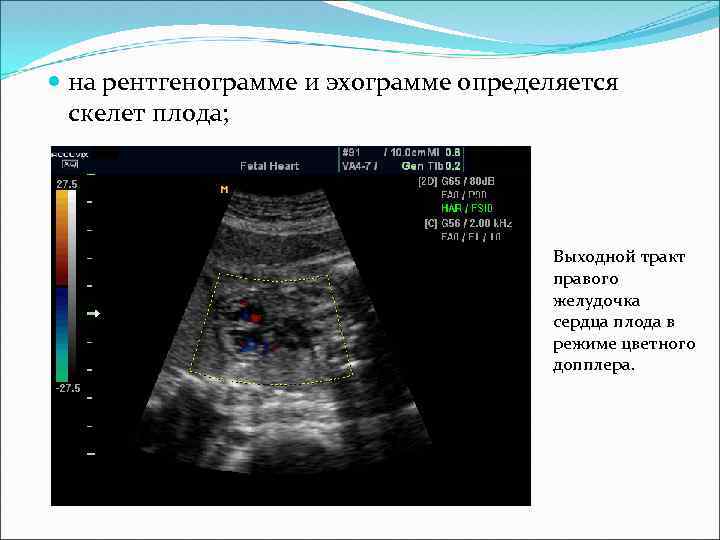

на рентгенограмме и эхограмме определяется скелет плода; Выходной тракт правого желудочка сердца плода в режиме цветного допплера.